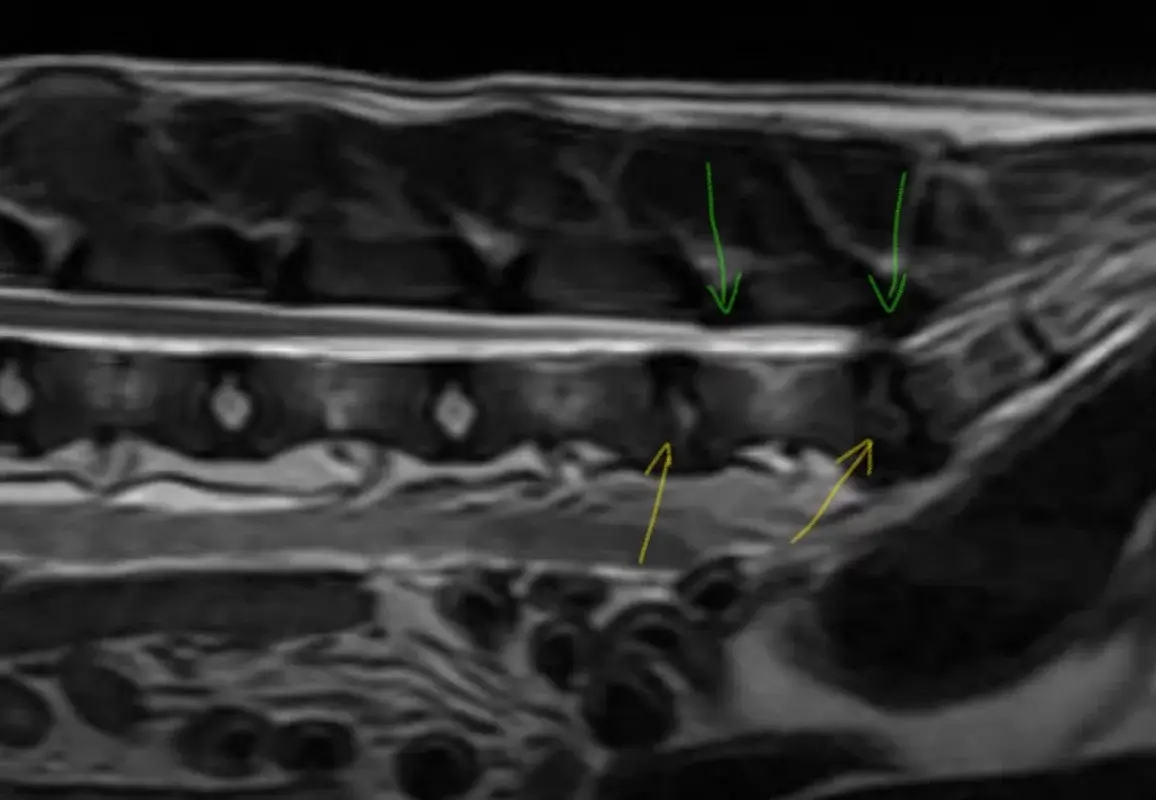

Ja, @Harz2024 , es gibt schon ein MRT, da kam die Diagnose Bandscheibenvorfall L7 - S1 mit beidseitiger Stenose des Wirbelkanals. (Original: Hernia discal L7-S1 con estenosis foraminal bilateral)

Auf dem MRT Bild sieht man, wie die betroffenen Bandscheiben degeneriert sind (gelbe Pfeile) und die Stenose ist die Verengung des Kanals, bzw auch von oben wird hereingedrückt, (grüne Pfeile)